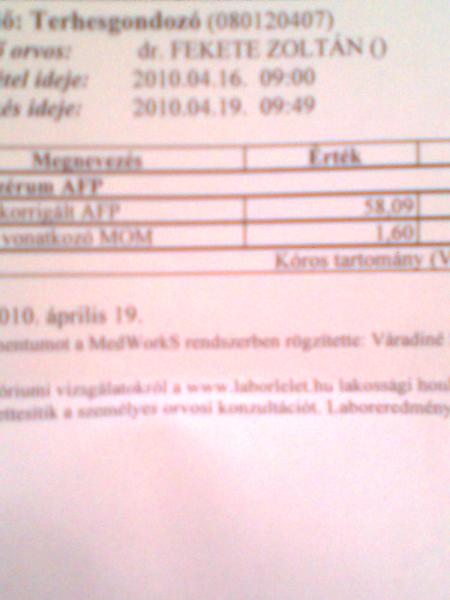

Én ma voltam afp vérvételen (majdnem elaludtam...

) és mondta a nő, aki levette a vért, hogy minden kismamával közli, hogy ez egy elavult vizsgálat és ne ijedjenek meg ha "rossz" lesz az eredmény, csak egyszerűen az oep nem hajlandó támogatni a normális értékelhető vizsgálatot.